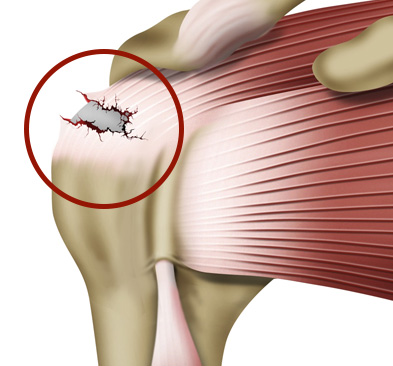

이런 회전근개가 하나 또는 그 이상 파열되는 것을 회전근개 파열이라고 합니다.

회전근개 파열의 원인은 여러 가지가 있으나

반복적인 움직임이나 과도한 사용으로 인해 근육에 스트레스가 가해지거나, 염증이나 건염 등의 원인으로 힘줄이 약해지면 파열의 위험이 생깁니다.